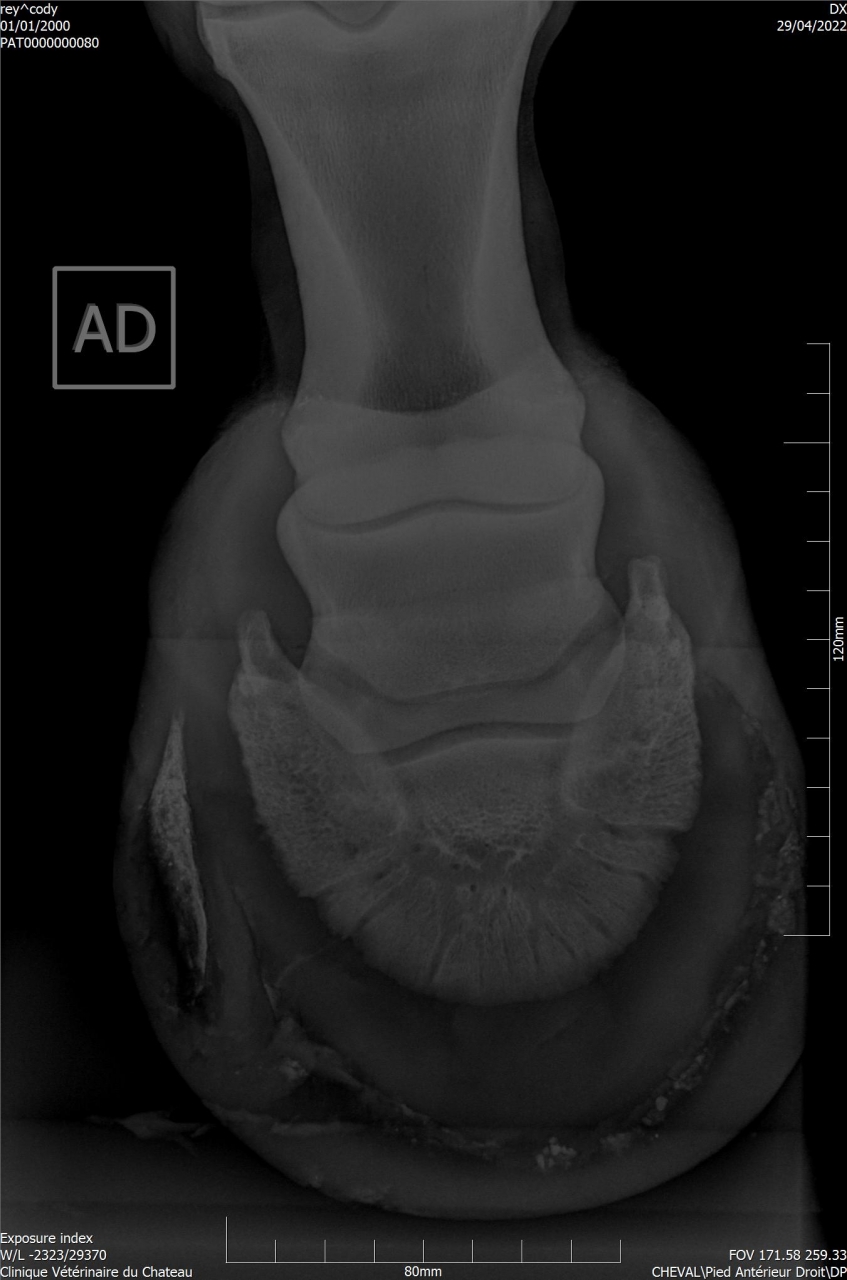

| Dire merci | Je remonte le post Mon cheval a été diagnostiqué naviculaire, il y a des fossettes synoviales. Ma véto préconise une infiltration avec du Tildren ou de l’Osphos. Aujourd'hui mon cheval a été ferré : antérieurs avec oignons et plaques en cuir, ferrure normale aux postérieurs. Voici les radios : ![]() ![]() ![]() ![]() ![]() |

| Dire merci | Les radios LM montrent une pince trop longue et pas de roll/ breakover Agir sur cela soulagera déjà énormément l’arrière du pied ! Sur la dp 60 on voit une zone noire circulaire Aurais tu une photos vue solaire stp ? Y a t’il fourmilière/évasement important voire un abcès récent ? |

| Dire merci | Je n'ai que ça comme radios ... Il y a des fourmilières aux 2 antérieurs. |